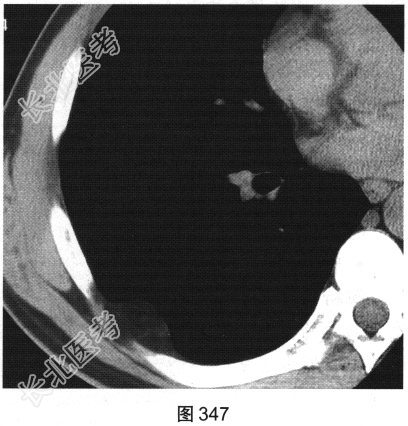

患者男性,43岁,平素健康,偶感深吸气时右后背部不适。近期该患者单位组织体检,在行胸部CT扫描时发现胸壁肿物,见图346、图347。

- 多项选择题2.依据该患者的CT表现特点,最可能的诊断是( )

A、胸壁脂肪瘤

B、胸壁纤维肉瘤

C、胸壁脂肪肉瘤

D、胸壁横纹肌瘤

E、胸壁包裹性积液

F、胸壁转移瘤

G、胸壁神经源性肿瘤